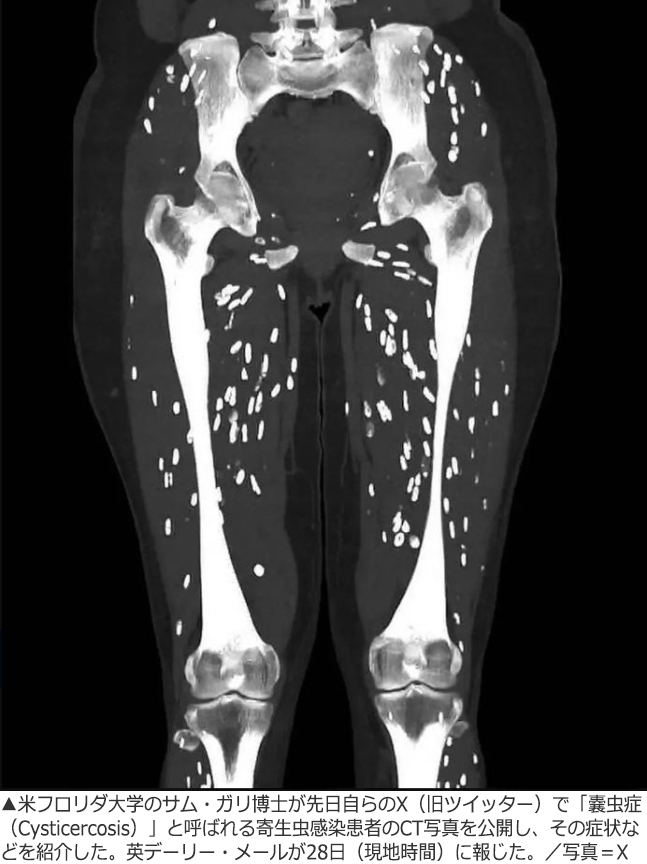

生焼けの豚肉を食べて寄生虫に感染、米研究者が患者のCT写真を公開して注意喚起(2/2)